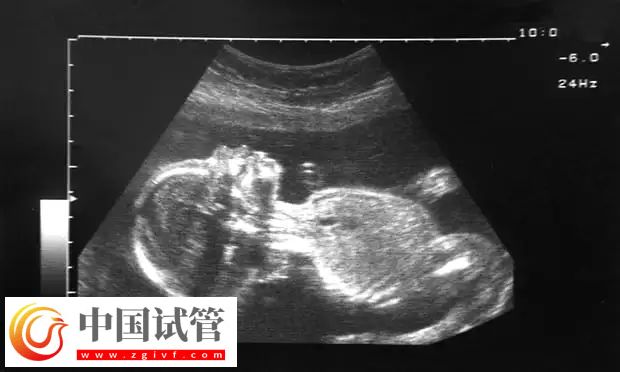

孕早期是一個(gè)非常危險(xiǎn)的時(shí)期,這個(gè)大家都知道。在孕早期的時(shí)候,很多女性都特別注意。到了孕中期,也就是試管4個(gè)月時(shí),很多人都認(rèn)為應(yīng)該松一口氣了,但是殊不知孕中期往往也會(huì)出現(xiàn)出血的情況。這種情況一旦是出現(xiàn),就意味著女性的身體出現(xiàn)了問題:

先兆流產(chǎn)可發(fā)生在妊娠早、中期,陰道出血是妊娠中較常見的危險(xiǎn)征兆,因此要引起高度重視。陰道出血量視流產(chǎn)類型而異,多數(shù)孕婦伴有下腹陣發(fā)性墜痛;隨著病情的發(fā)展,陰道出血可逐漸增多,同時(shí)會(huì)出現(xiàn)腹痛次數(shù)增加、程度加重腹部感到寒冷、有時(shí)感覺不到胎動(dòng)等癥狀。如出血量大、下腹部疼痛頻而重時(shí),不論晝夜應(yīng)立即送往醫(yī)院。

葡萄胎孕婦陰道出血,一般始于閉經(jīng)后6-8周,多為斷斷續(xù)續(xù),并反復(fù)出現(xiàn)。血呈暗紅或棕褐色,亦可為少量咖啡色分泌物。出血量多少不一,一般由少量逐漸增多,血中帶有水泡樣物。在大量的陰道出血前,因子宮內(nèi)出血與水泡樣物增多、增大,使子宮迅速膨大,故常有腹部持續(xù)性脹痛。

胎盤異常

前置胎盤和胎盤早剝都是產(chǎn)科非常兇險(xiǎn)的并發(fā)癥。如果胎盤從子宮內(nèi)膜脫落、分離等都會(huì)引起孕婦懷孕中期出血。如果胎盤脫落,胎兒就得不到氧氣和營(yíng)養(yǎng),此時(shí)孕婦就要采取措施,應(yīng)該盡快就醫(yī),否則會(huì)引起孕婦失血過多休克、死亡。